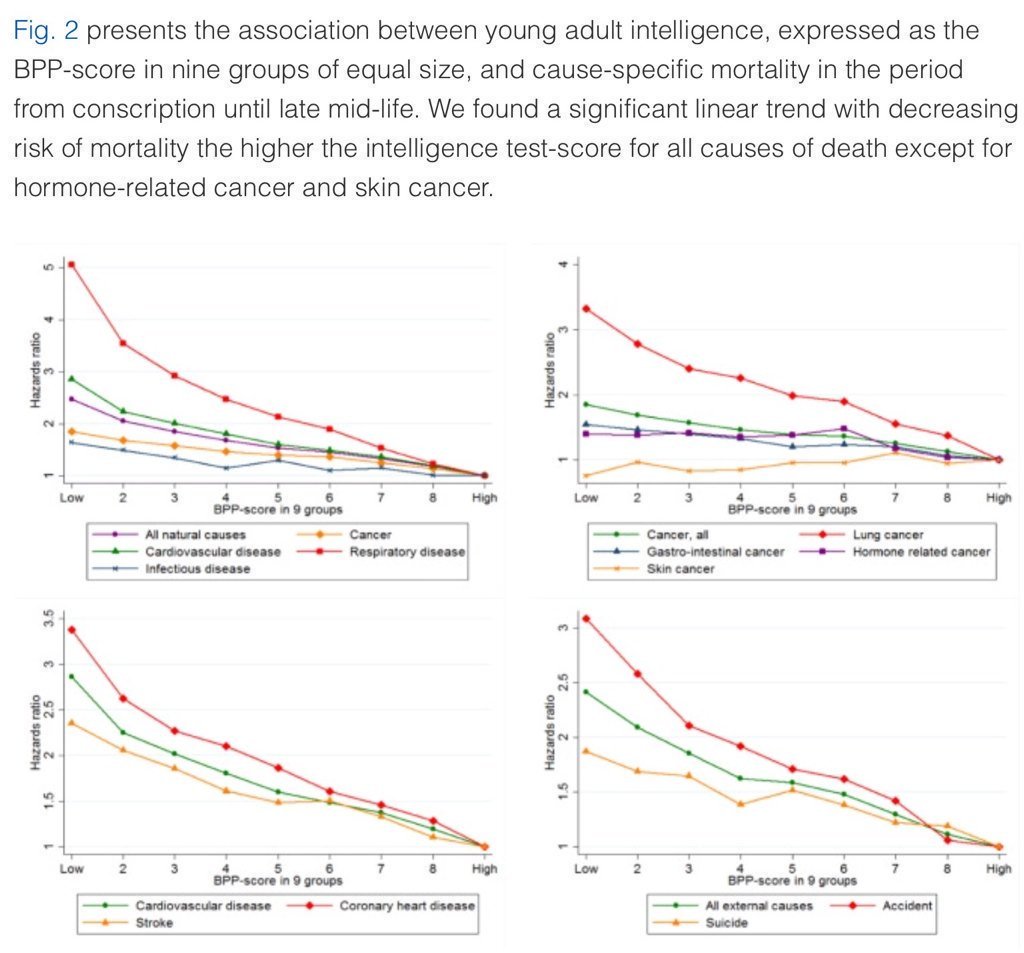

5. Higher IQ is associated with a lower risk of death from most causes, including cardiovascular disease, respiratory disease, most forms of cancer, homicide, suicide, and accident. https://t.co/PJjGNyeQRA (N = 728,160)

5. Higher IQ is associated with a lower risk of death from most causes, including cardiovascular disease, respiratory disease, most forms of cancer, homicide, suicide, and accident. https://t.co/PJjGNyeQRA (N = 728,160)